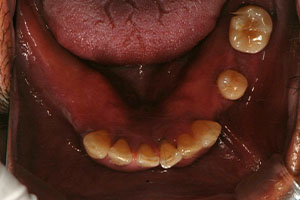

치료증례 전후사진

Before & After